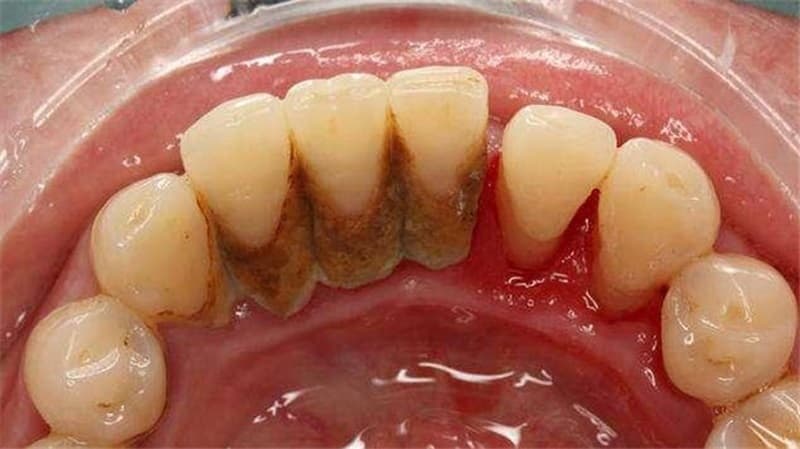

– Các bệnh về răng miệng khác: Sự tác động của vi khuẩn và quá trình hình thành cao răng ăn sâu vào chân răng sẽ gây ra các bệnh về nha chu, tình trạng tụt lợi, viêm lợi, lợi chân răng kích ứng thường xuyên chảy máu,….

Cao răng nhiều gây viêm chân răng, tụt lợi và viêm nha chu